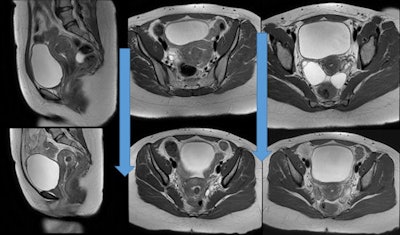

Our group of 23 pregnancies was small, but did confirm successful pregnancy after UFE. The 45.7% pregnancy rate in women younger than 40 years old who achieved a term pregnancy compares favorably with women who underwent myomectomy via a number of techniques. Of the women in the cohort who did conceive, subsequent birth proceeded normally (86%).

We compared this to abdominal myomectomy, in which the term pregnancy rate ranged from 10% to 46%, laparoscopic myomectomy (16% to 33%), and hysteroscopic mymomectomy (8% to 35%). This means the implications for uterine artery embolization as a primary treatment for uterine fibroids as a fertility-sparing technique is favorable. Our preliminary data suggest that fertility is further enhanced in women who underwent UFE as a first procedure to control uterine fibroids.

This study is significant, because it shows comparable fertility rates between the two primary uterus-sparing treatments widely available to treat fibroids: UFE and myomectomy, which is considered the gold standard for symptomatic fibroids in women who wish to conceive.

The results are surprising, because other old small studies have favored myomectomy over UFE for women who want to conceive. In this study of 210 women, UFE had a fertility rate of 47%. This is comparable to the fertility rate for myomectomy, which is 48%. The study proves that UFE not only allows women who were unable to conceive to become pregnant, but also allows them to have normal pregnancies with similar complication rates as the general population despite being a high-risk group. In the future, UFE will probably be a first-line treatment option even for women who wish to conceive and are unable due to the presence of uterine fibroids.